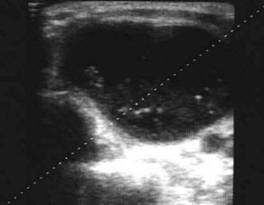

Femeie 19 ani. Leziune marcant hipoecogen cu intarire posterioara, de 16x20x26mm (4 cc) in lobul drept.

Examen citologic: macrofagi, fara tireocite.

Femeie 17 ani. Voluminoasa tumefactie (32x40x45mm, 29 cc) in lobul stang, intens hipoecogena, cu echo densitati in interior, intarire posterioara. Deviatia tracheei spre dreapta.

Examen citologic; chist coloid

Aceeasi pacienta in timpul si dupa citoaspiratie